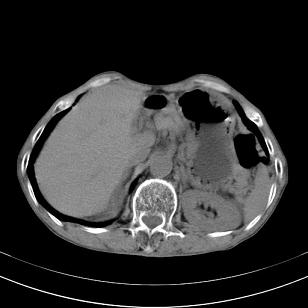

标题: 男,65岁,反复右上腹痛, [打印本页]

标题: 男,65岁,反复右上腹痛,

胃镜提示十二指肠占位